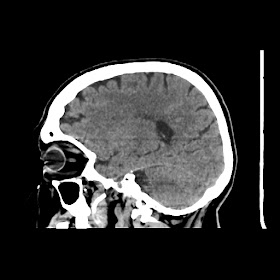

A 75 years old woman with DM-2 since 3 years

Patient O/E images:

C/O: Breathlessness X 2-3 day's

H/O: unconsiouness since few hour's at home around 10:30 pm

K/C: DM / HTN since 2-3 year's